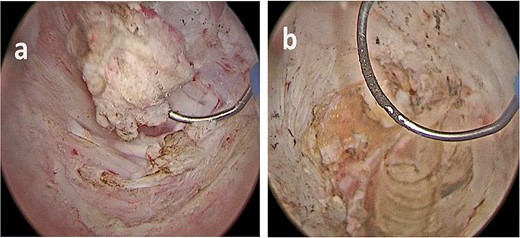

Histopathological and immunohistochemical analysis showed a fusocellular neoplasm composed of cells with elongated nuclei expressing S100 protein. In contrast, CD34 and NF markers were negative and compatible with schwannoma. This appeared on the left seminal vesicle, the prostatic cognitive target, and the bladder lesion (Fig. 4). After surgery, the patient experienced stability in his storage urinary symptoms and showed no signs of recurrence after 1 year of follow-up.

(a) Schwannoma (20×); alternating compact Antoni A areas (center) with nuclear palisades, known as Verocay bodies and loose Antoni B (periphery) areas. Note some characteristic hyalinized blood vessels. (b) Schwannoma (40×). No mitosis, nuclear atypia or necrosis are seen, in accordance with the benign nature of the neoplasm. (c) Very low proliferation index (Ki67); scattered positive cells. (d) Diffuse positive immunoreactivity for S100.

Schwannomas are the most common benign tumors of peripheral nerves [2]. They are encapsulated tumors originating in Schwann cells. Histologically, they are composed of alternating areas of dense cellularity termed Antoni-A regions and areas of myxoid matrix termed Antoni-B regions. Immunohistochemical staining is typically positive for S-100 and negative for CD34, epithelial markers, and smooth muscle-specific actin. [3]. NF is usually positive in other diseases like neuroblastoma or medulloblastoma. Malignant progression is rare; however, a pathological variant (melanotic schwannoma), in which malignant transformation can occur, has been described [3, 4]. Most schwannomas are single lesions and sporadic, affecting individuals of all ages but with a peak occurring between 20 and 50 years, with similar prevalence in both sexes [5]. When these lesions are multiple, they are usually associated with familial syndromes such as neurofibromatosis type 2, schwannomatosis, and Carney complex [6]. They can be found more commonly not only on the head and neck but also on any other body regions, such as limbs, chest, abdomen, retroperitoneum, and pelvis. Schwannoma of the seminal vesicles is extremely rare, with only 12 cases described to the best of our knowledge. The first case was described by Iqbal et al. [7]. They are usually asymptomatic and diagnosed incidentally or when the mass becomes large enough to compress adjacent structures. The diagnostic algorithm usually includes an imaging exam (CT scan and/or MRI) to characterize the location, size, and extension of the tumor. Most cases reported to date included a transrectal biopsy for histological characterization. Autieri et al. [8] described a case of a transrectal biopsy of a schwannoma of the seminal vesicle complicated with an abscess that needed urgent drainage. Since we considered the possible presence of prostate cancer, the biopsy was essential to obtain a definitive diagnosis. Surgery can be resolutory, but we decided, in accordance with the patient, to adopt clinical surveillance and perform a pelvic RM yearly until new symptoms appear.